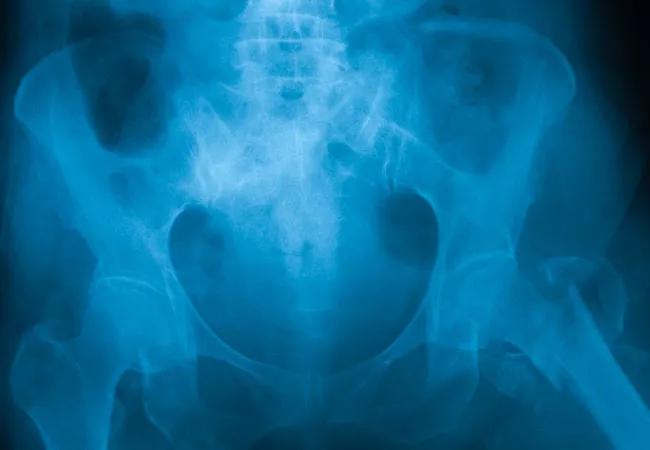

Fragility fractures beget more fractures. People who have had a fracture due to osteoporosis are twice as likely as their peers to have another, according to the World Health Organization.

In a chart review of 100 Cleveland Clinic patients (average age 71.8) hospitalized for fragility fracture of the hip, vertebra, leg or pelvis between 2015 and 2018, 53 were readmitted within one year, 26 with a second fracture.

“While 73% of these patients had not been treated for osteoporosis before their first fracture, 72% still were not treated for osteoporosis within two years after the fracture,” says Dr. Miklowski. “In fact, 73% didn’t even have a bone density scan after the fracture.”